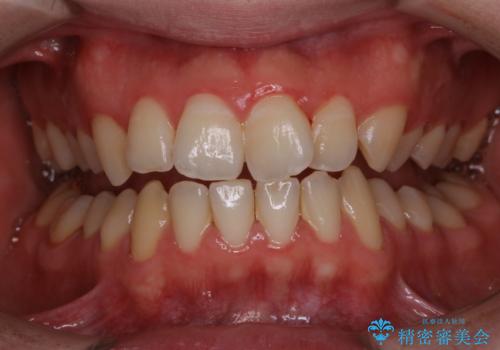

痛みや症状がないため、長年にわたり歯科に行かずメンテナンスなどを行っていないと、将来的に残っている歯の本数が格段に少ない傾向があることが分かっています。

歯磨きの際の出血、お口の中の違和感・変化などを放置していると、のちに歯を失ってしまう原因になることもあります。

歯周病の原因は、口の中に棲む歯周菌です。歯周病菌や歯周病菌の出す毒素が引き起こす炎症によって歯茎が腫れ、歯を支えるセメント質、歯槽骨や歯根膜が破壊されて、ついには支えを失った歯が抜けてしまうという怖い病気です。

セルフケアだけでは、歯周病を治したり予防したりすることは困難です。

歯科医院で定期的にクリーニングを行い、歯石除去や細菌に汚染された歯根面の掃除が必要になります。